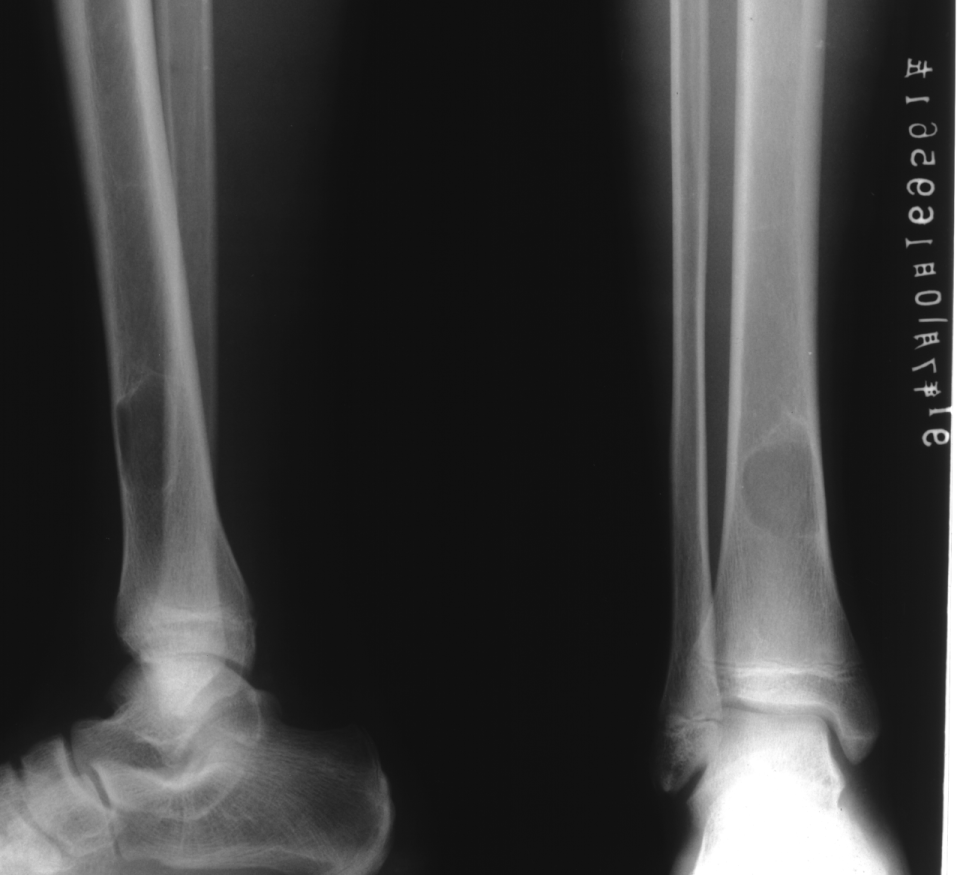

地图样破坏是指肿瘤组织在一个局部呈团块状生长造成界限清楚的骨质破坏(图 1、图 2、图 3、图 4)。病灶可位于骨的中心或一侧部位,呈圆形、卵圆形密度减低区,与正常骨质分界清晰,边缘可有或无硬化带围绕,骨的形态无变化,病灶内可完全透亮或可见粗细不均、大小不等的残留骨嵴,内缘可光滑或呈分叶状压迹。地图样破坏见于大多数良性肿瘤和肿瘤样病变如单纯性骨囊肿、骨纤维结构不良、血管瘤等、也可见于部分恶性骨肿瘤如骨转移瘤、骨髓瘤等。

图 3.地图样破坏:骨内脂肪瘤

图片